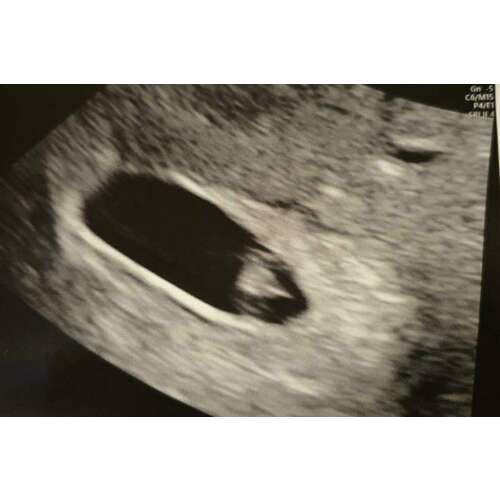

Dat is je baby 🥰 van 2mm. Als je rechtsonder kijkt zie je 0,22cm staan. En dat is de lijn die die 2 gele plusjes geeft

Dat is je baby 🥰 van 2mm. Als je rechtsonder kijkt zie je 0,22cm staan. En ...